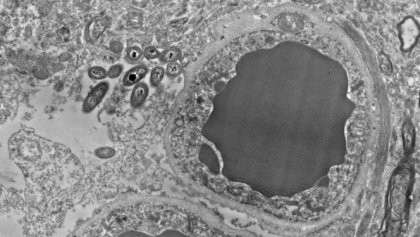

Tanto en uno como en otro estudio, se observaron la presencia de bacterias en el cerebro humano y en el de los ratones, en situaciones no infecciosas o traumáticas.De hecho, se encontraron en varias zonas cerebrales. Principalmente en la sustancia negra, el hipocampo y la corteza prefrontal; y muy poca cantidad en el estriado. Además, ninguno de los cerebros examinados mostraba inflamación.

Imagen principal de Rosalía Roberts, Courtney Walker y Charlene Farmer